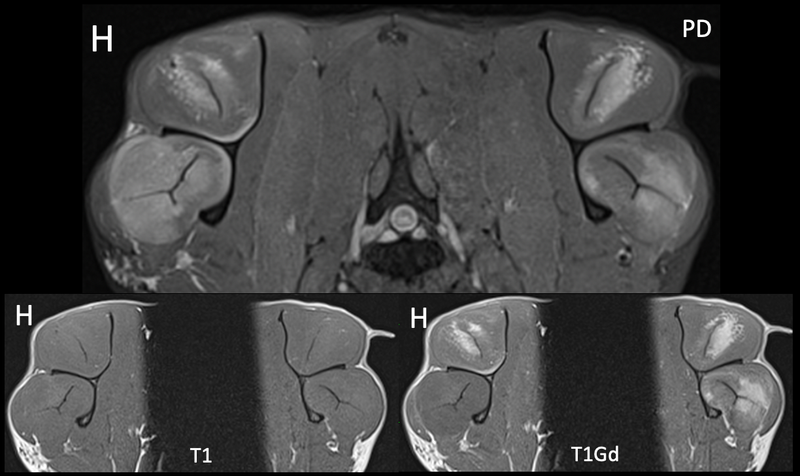

Endelig er vi i gang med kasus igjen, og vi starter høstsesongen med denne godbiten som ble sendt inn til oss fra AniCura Jeløy Dyresykehus. Ha gjerne denne i bakhodet hvis det kommer inn jakthunder eller andre veldig aktive hunder med halthet fra skulder i høst! Signalement: Engelsk setter, Hannhund, 3 år Anamnese: Akutt halt høyre frambein etter jakt Kliniske funn: 4-5/5 grader halt høyre frambein, smerte ved fleksjon av skulder. Ikke medial instabilitet. Mediolaterale og craniocaudale røntgenbilder av begge skuldre er uten unormale funn.